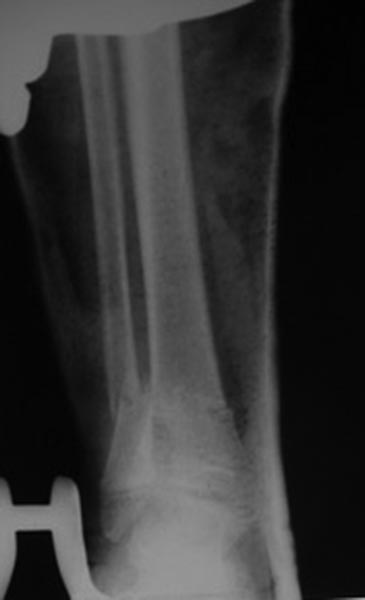

Переломы оскольчатые обеих бёдер в н/3, открытые. Раны ушиты в отличном состоянии.

На одном бедре межмыщелковый перелом и там мыщелки немного разъехались. Голень там тоже сломана в н/3 обе кости. Снимок голени в боковой проекции сделан не был.

Глубокоуважаемый Игорь. Есть ли в вашем отделении ЭОП? Переломы бёдер не простые. Я бы не стал рассчитывать на скелетное вытяжение. Не очень понятно где какое бедро. Левые снимки – по моему мнению бедро надо оперировать с артротомией: необходимо убрать осколки по передней поверхности перелома – они гарантировано будут мешать движениям. Малоинвазивное удаление может быть неудачным. Синтез мыщелков имеющимися у Вас спицами под контролем глаза и пальца. Кстати, в суставе могут быть обнаружены различные неожиданности. Общую фиксацию можно осуществить в АНФ Илизарова с встречной компрессией мыщелков. Правые снимки. Тоже высокоэнергетический перелом и критическое смещение отломков. Так оставлять, ИМХО, не стоит. Велика вероятность массивной интерпозиции между отломками. Отломки ротированы и это может вызвать нарушение сращения,ремоделирования кости. В качестве варианта: наложение АНФ Илизарова, разрез, «ручная» репозиция отломков «по месту». Дистальные перекрещивающиеся спицы я бы провёл через мыщелки бедра. АНФ будут оптимальны в спице-стержневом исполнении. С уважением!